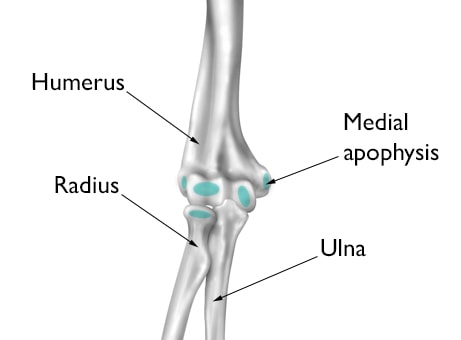

growth areas of child's elbow

The growth areas of a young athlete's elbow are vulnerable to overuse injury. This illustration shows the elbow from the front, with the arm straight and palm forward. The growth areas of an immature elbow are highlighted in blue.

Reproduced and adapted with permission from J Bernstein, ed: Musculoskeletal Medicine. Rosemont, IL, American Academy of Orthopaedic Surgeons, 2003.

Medial apophysitis. One of the most common elbow problems in active children is medial apophysitis, often referred to as "Little Leaguer's elbow." Medial apophysitis causes pain at the bony bump on the inside of the elbow. The bump, called the medial epicondyle, is at the end of the humerus bone and contains a growth plate called the medial apophysis. Muscles that control wrist motion attach to the medial epicondyle, and excessive overhand throwing can irritate and inflame the growth plate.